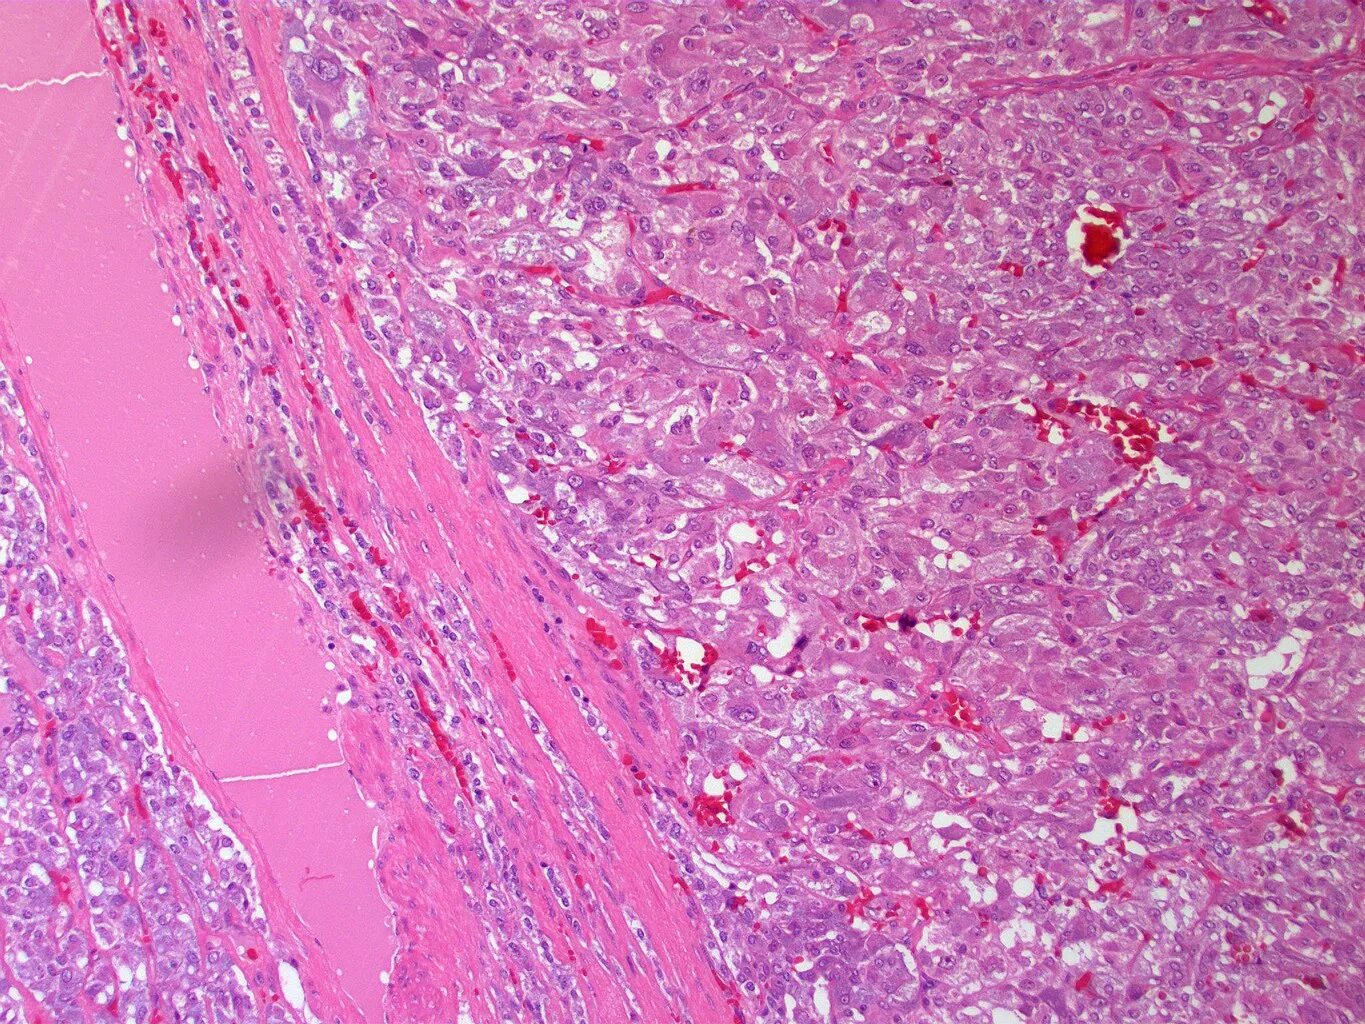

Д гистология